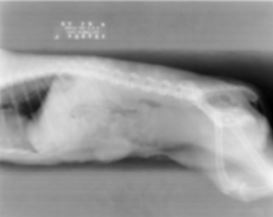

14

Artifact and fix?

Moire - Sampling read at the level of the grid lines

Oscilate grid

Grid reduction algorithms

Grid oriented perpendicular to plate reader